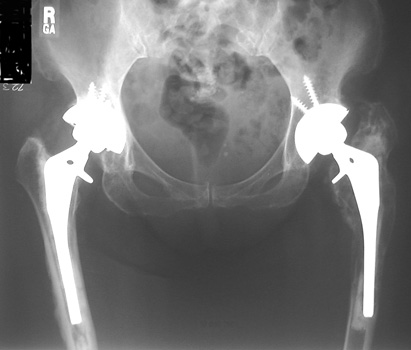

ACETABULAR COMPONENT

Severe protrusio in patient with RA